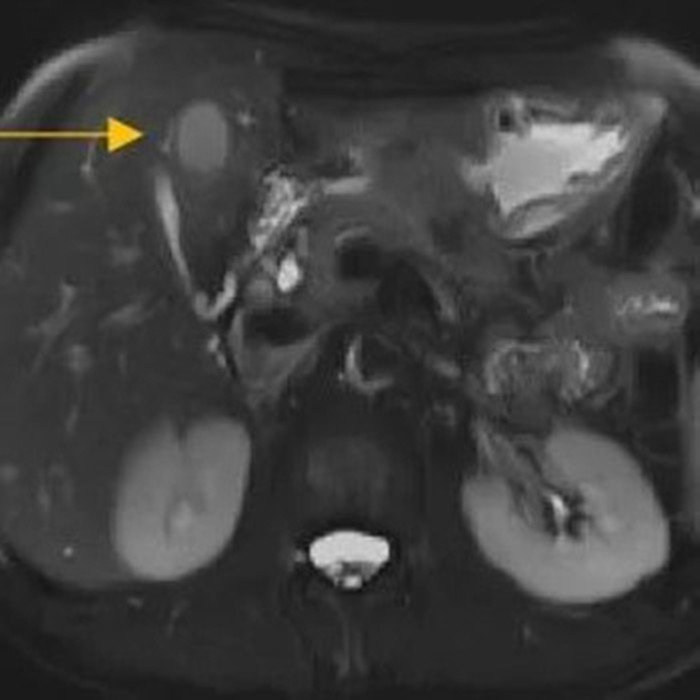

住院后經(jīng)胸腹部CT檢查,提示周先生胃部巨大腫塊穿破胃腔,可能累及到結腸,同時合并有胃旁淋巴結轉移、肝臟的轉移??吹竭@個檢查報告后,周先生和他的愛人一下子就泣不成聲了。

治療前的腹部CT提示胃

治療前肝臟的轉移灶

經(jīng)過6個周期,前后4個月的治療,周先生再次復查CT,提示胃部腫瘤,轉移的胃旁淋巴結、肝臟腫瘤都有明顯縮小,營養(yǎng)狀況良好,能正常進食,體重增加了6斤,精神狀態(tài)比原先好了很多。